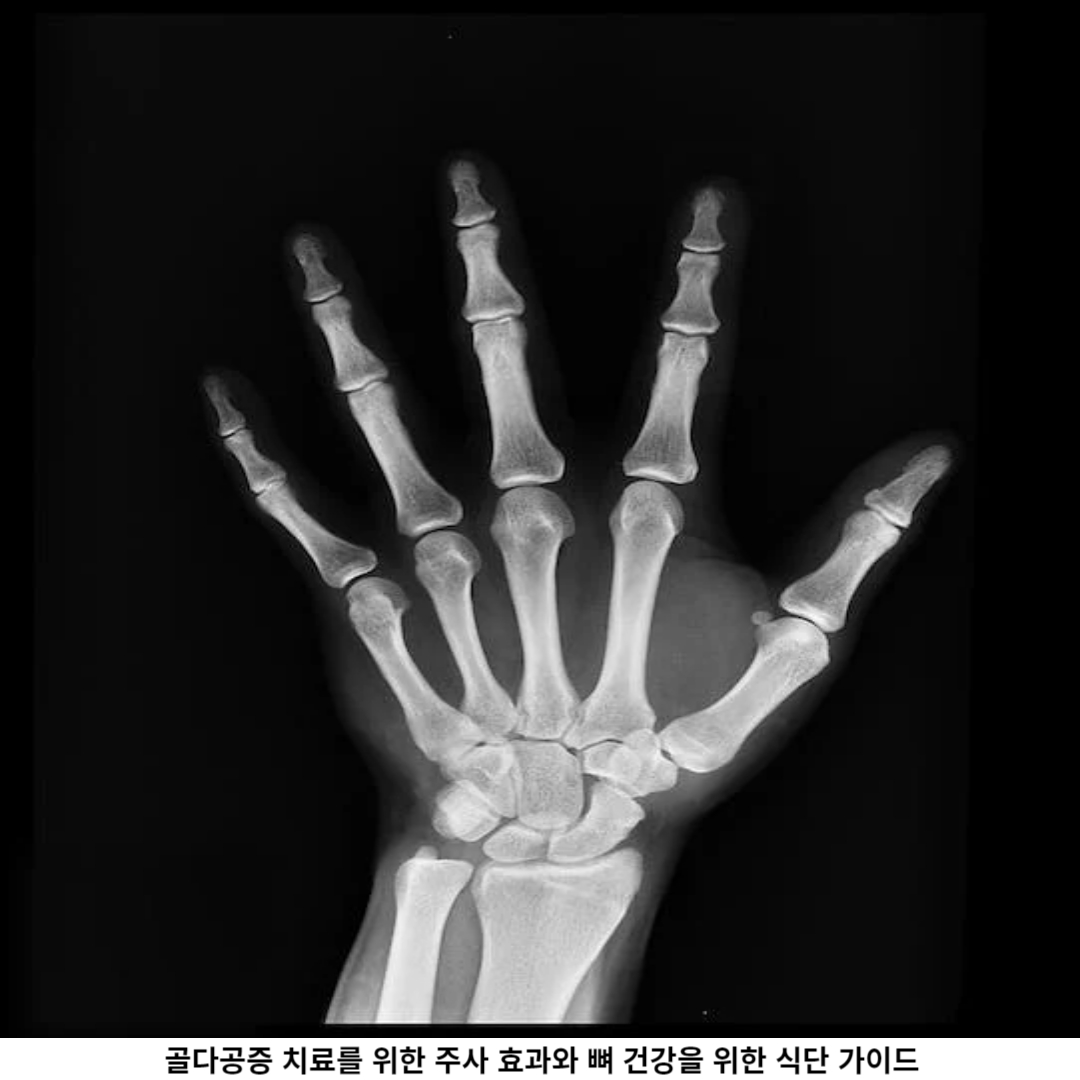

3. 골다공증 주사와 부작용 알아보기

골다공증 주사는 골다공증의 치료와 예방을 위해 사용되는 주사입니다. 이 주사는 주로 골다공증 예방 약물인 비스포스포네이트를 사용합니다. 비스포스포네이트는 뼈 손실을 줄이고 새로운 뼈 형성을 만들어 뼈를 강화시키는 효과가 있습니다.

골다공증 주사는 주로 6개월에 한 번씩 투여되며, 의사의 처방에 따라 다르게 처방됩니다. 주사는 정해진 날짜에 맞추어 병원에서 접수하거나 의사와 상의하여 진행할 수 있습니다.

주사의 부작용으로는 발생되는 것은 소화장애, 근육통, 발열 등이 있을 수 있으며, 이러한 부작용이 나타날 경우 의사에게 즉시 상담해야 합니다. 또한, 주사 처방 전에는 주사의 효과와 부작용 등에 대해 충분히 숙지하고 주사를 받아야 합니다.